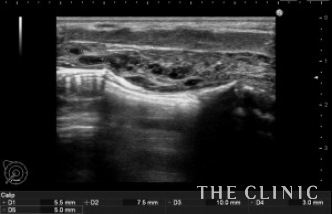

こちらは大胸筋内に細かくヒアルロン酸が注入されています。

エコー下にヒアルロニダーゼで溶解、吸引しました。